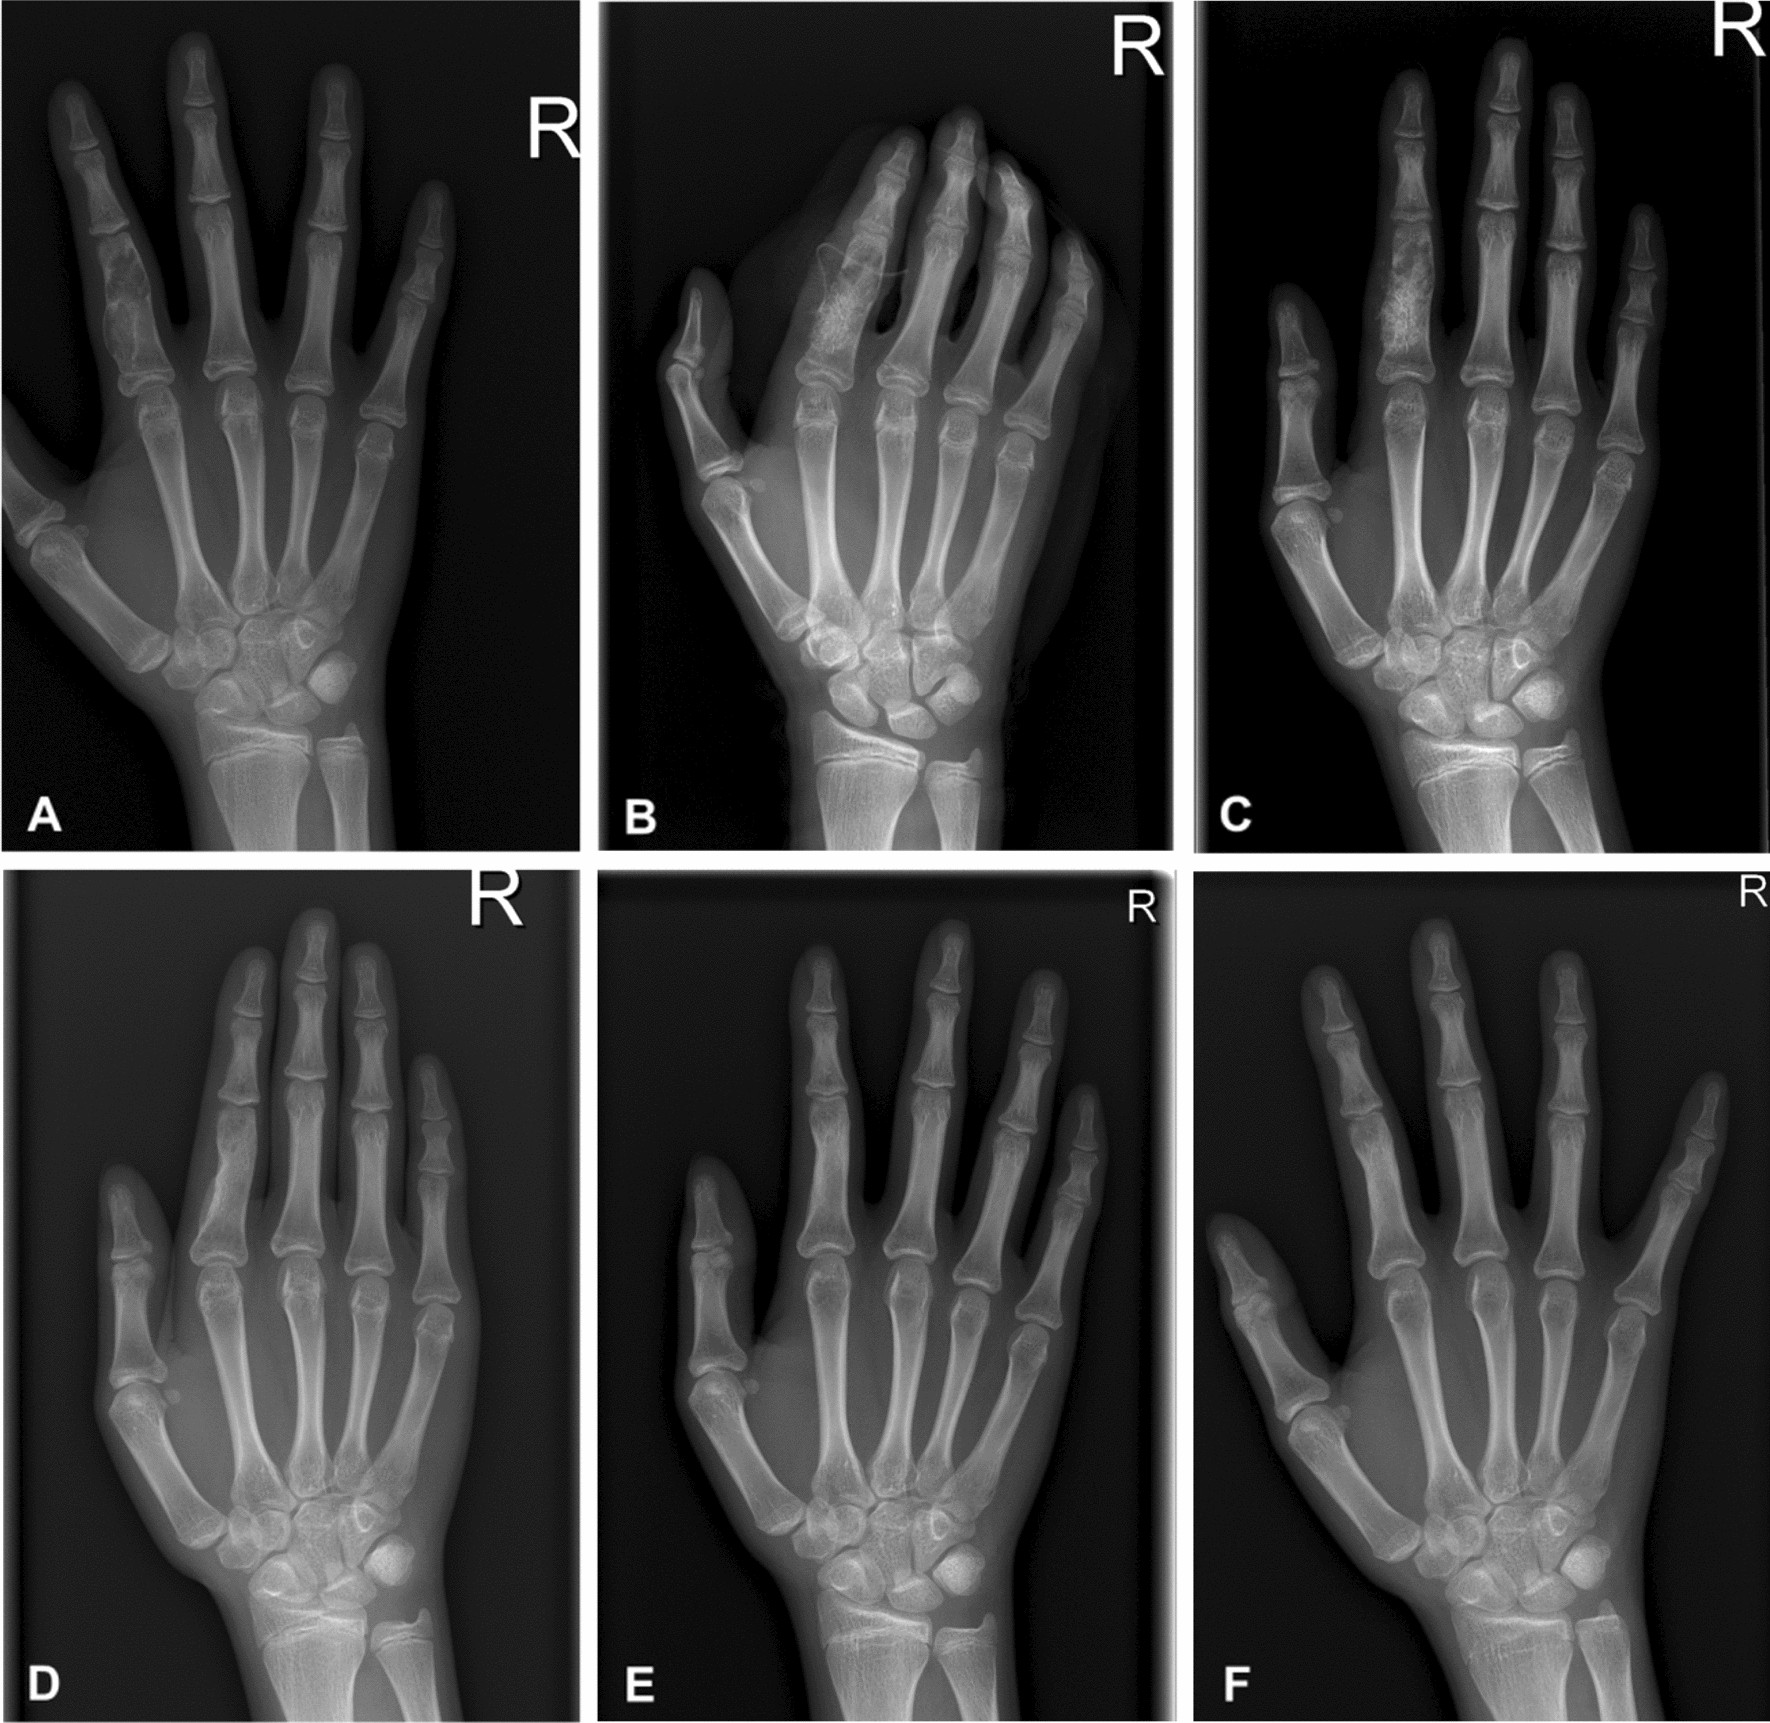

Figure 2

A 13-year-old female with enchondroma of polycentric and giant form in the proximal phalanx of the right index finger. Simple radiographs taken before surgery (A), immediately (B), 1 month (C), 2 months (D), 1 year (E), and 9 years (F) after surgery.